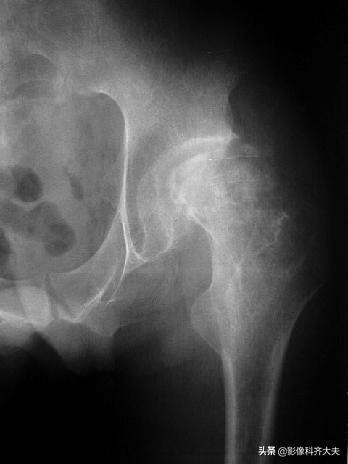

股骨颈嵌插骨折:老年人多见,断端常有错位或嵌入;可发生于股骨头下、中部或基底部;股骨颈短,肢体短缩,歪戴帽征;头下骨折引起关节囊损伤,影响血供,使愈合缓慢,甚至发生缺血性坏死。

股骨颈骨折伴有嵌入